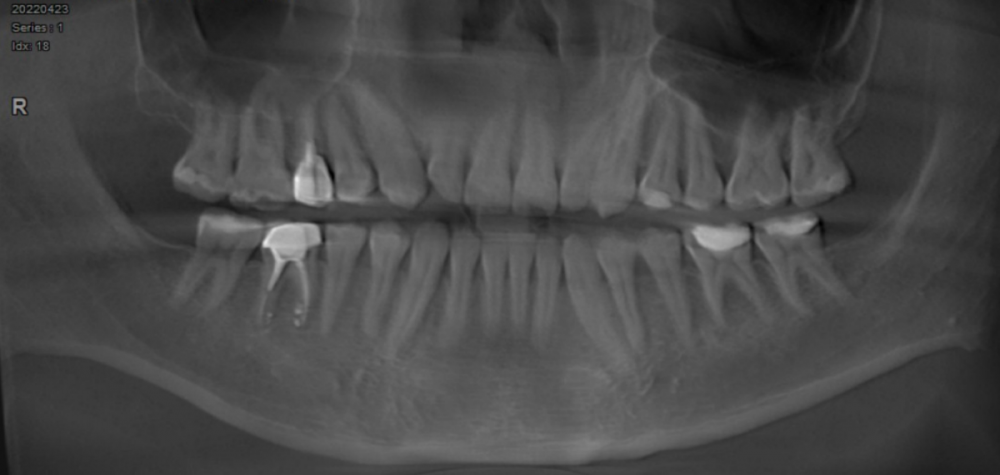

kamacho Опубликовано 23 февраля, 2024 Автор Поделиться Опубликовано 23 февраля, 2024 (изменено) Для истории. Сходил в клинику на консультацию ортопеда. Тот осмотрел коронки и свежий снимок кт. Сказал что коронки в полном порядке, что на 15 есть небольшой очаг воспаления и что киста в гайморовой пазухе скорей всего из-за него. Но те симптомы которые меня беспокоят наврятли из-за них. Заметил зубной камнеь на передних зубах, темноватое пятно на боку 36 зуба. Отправил к терапевту, открыть пломбу и проверить, нету ли там кариеса(и потенциально на 35 тоже). Жду вторника. Так же хотел сказать что проблема была довольно давно, но почему-то никто из врачей не хотел обращать внимание на 36 зуб, хотя я обращал их внимание на потемнение эмали ни раз. И уже отчаявшись ходить по разным клинникам к стоматологам пошел к гастроинтерологам, тем поставили диагноз - гэрб. Изменено 23 февраля, 2024 пользователем kamacho Ссылка на комментарий

kamacho Опубликовано 24 февраля, 2024 Автор Поделиться Опубликовано 24 февраля, 2024 (изменено) Так же приложу документ-опись риентгенолога по всем зубками с изображениями. снимок был сделан в 22 году. Наврятли кто-либо захочет перечитывать такое количество информации ради развлечения. Но для истории добавлю. Изменено 24 февраля, 2024 пользователем kamacho Ссылка на комментарий